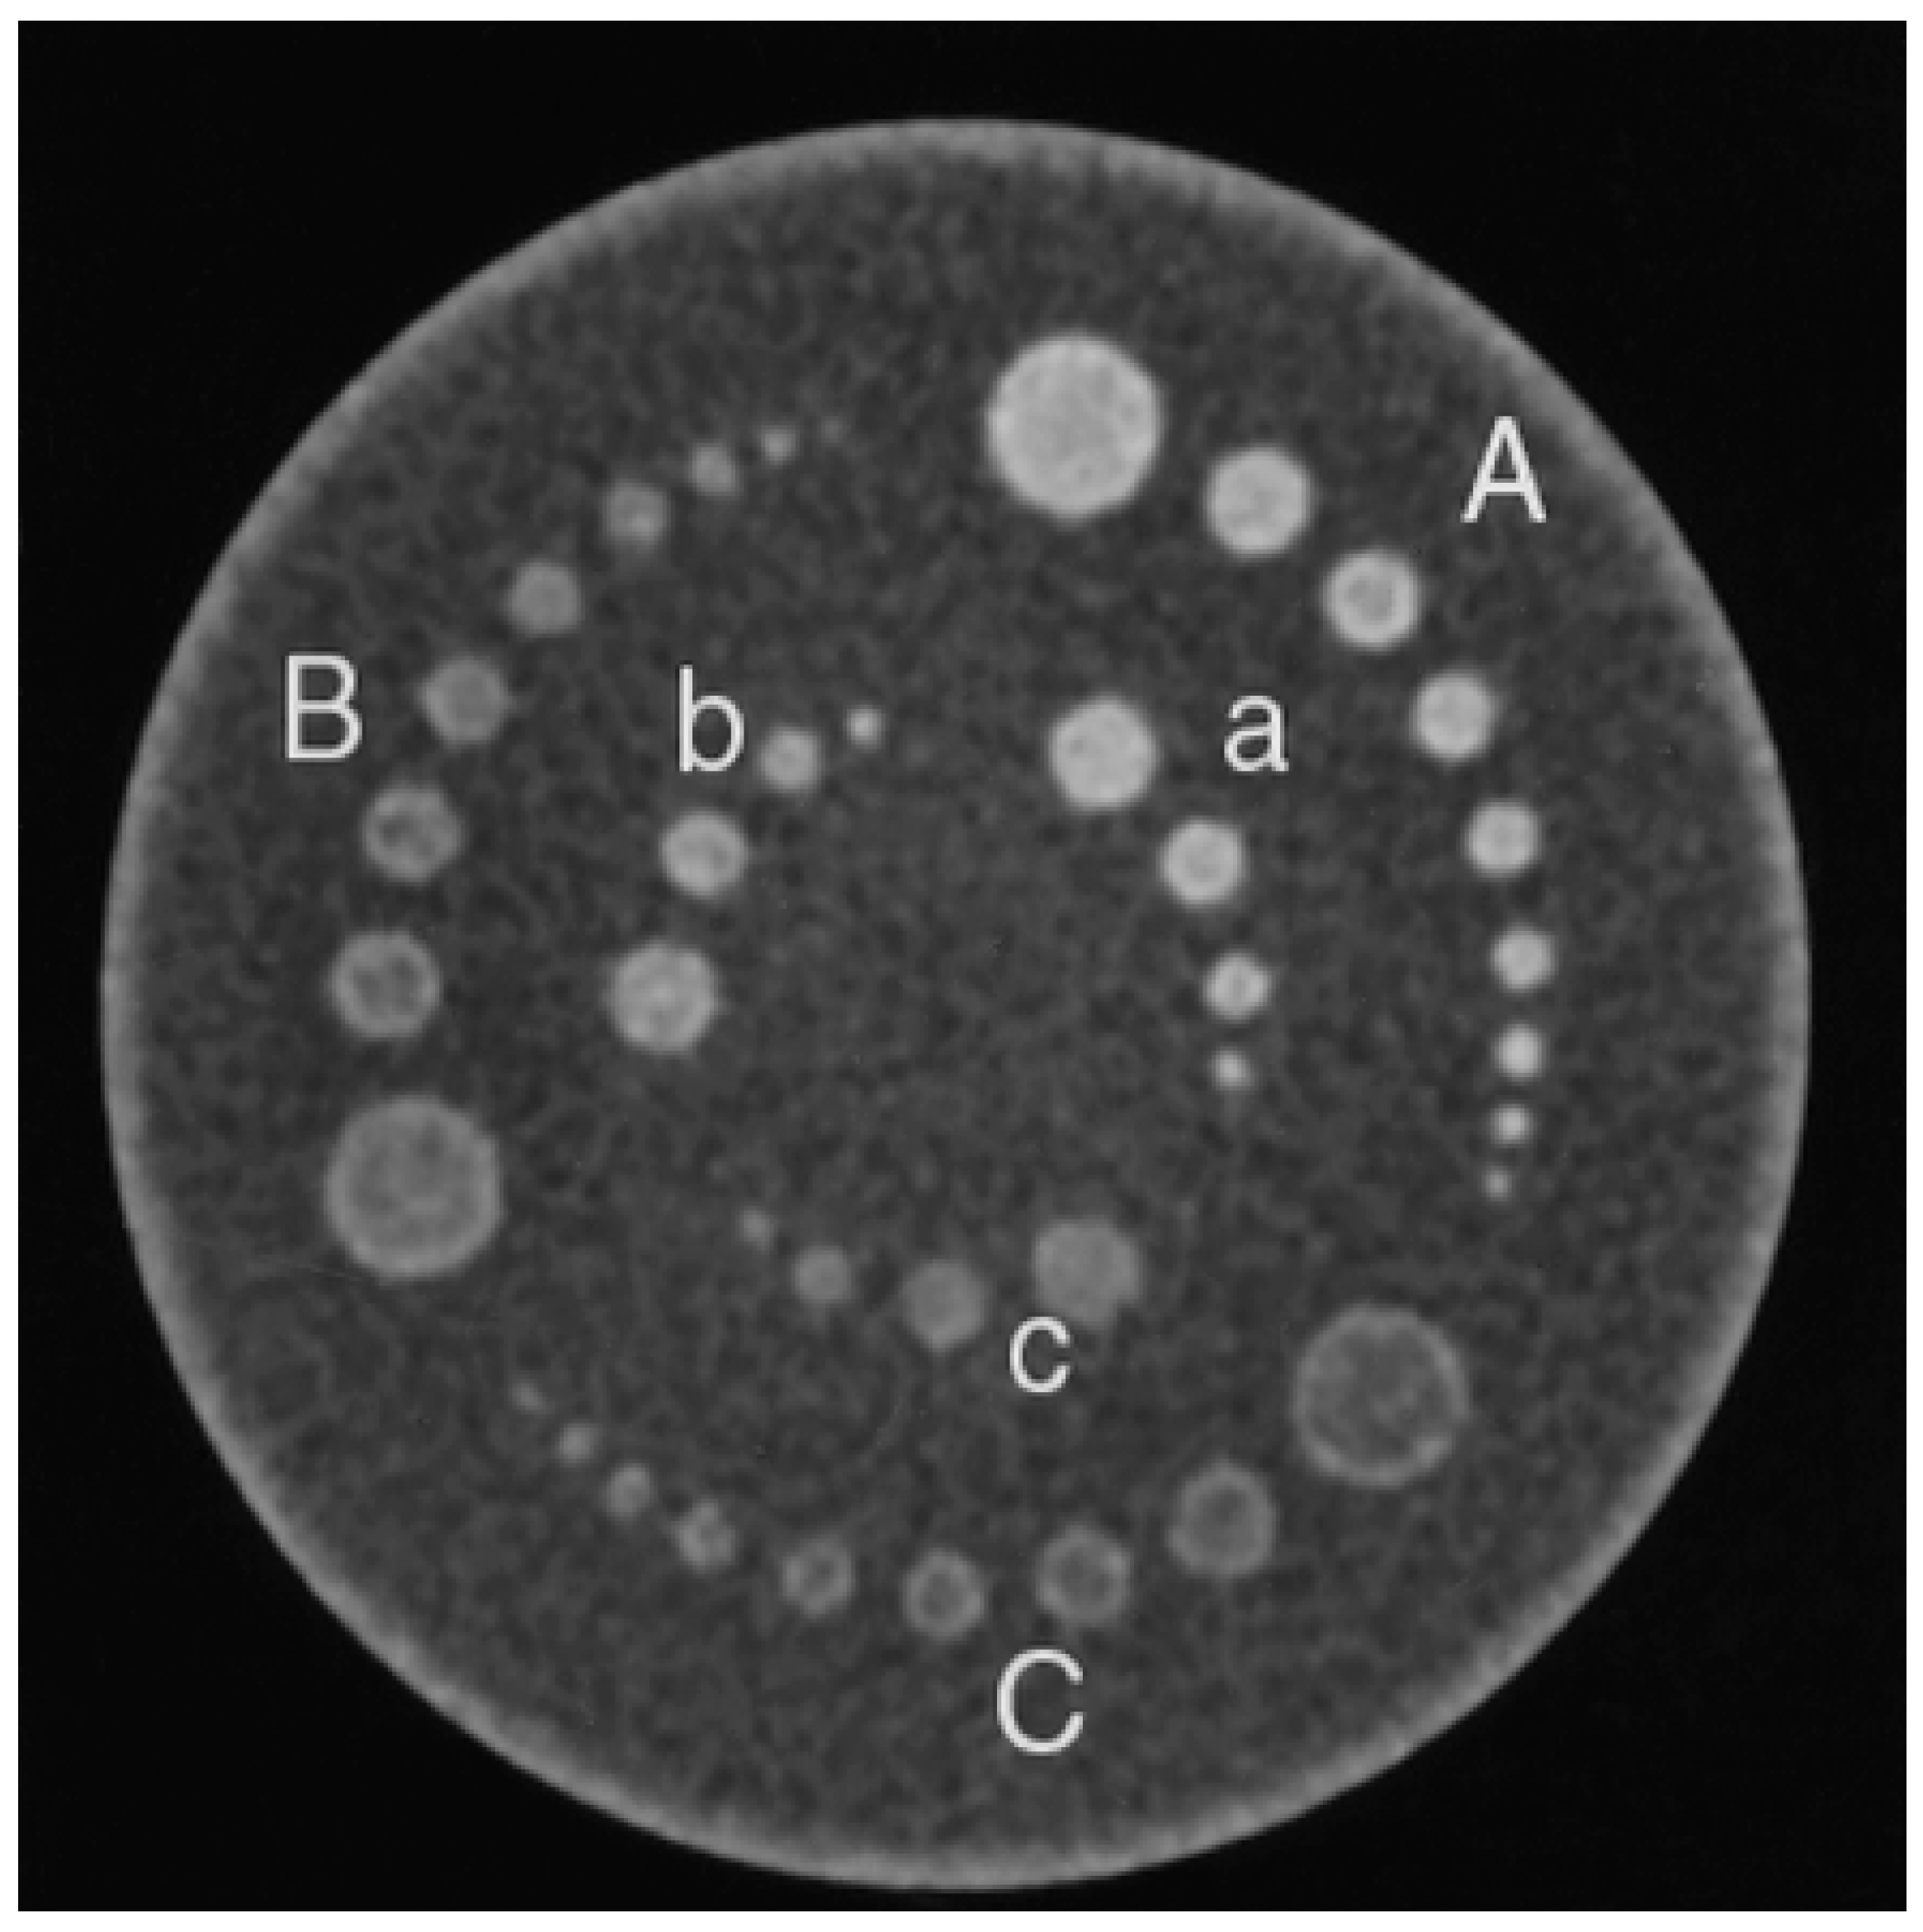

The Catphan® 600 (Phantom Laboratory, Greenwich, NY, USA)—known as the phantom—was mainly used in this study (Figure 1). In this, the image is developed from a medium of solid cast, produced using modules with a diameter of 15 mm. Each module assesses particular audits that correlate with the usage capability of the multidetector CT (MDCT). An LCD image module (CTP-515) was installed in the phantom for use in the experiment (as shown in Figure 1). The image shows a collection of sets of round, empty, low, multifaceted natural objects, arranged on two levels in the phantom. The objects were 40-mm high, were separated by different spaces (i.e., 2–9 and 15 mm) and were examined at three contrast levels (0.3%, 0.5% and 1%). The objects arranged around the outer level were chosen for study, those measuring 5–15 mm at a 1% contrast level, those 6–15 mm at a 0.5% level and those 7–15 mm at 0.3%. Thus, three specific contrast levels were used to examine the objects to assess the effect of object size on the CNR. The objects chosen for this part of the study were 1% separate level things for two purposes.

Figure 1.

A Phantom of low contrast module. Six different regions have been depicted where low contrast objects are put (A–C and a–c). Low cylindrical objects were placed in Regions A–C to contrast the difference in the objects in Regions A/a, B/b and C/c with the backgrounds of 1%, 0.5% and 0.3%, respectively.